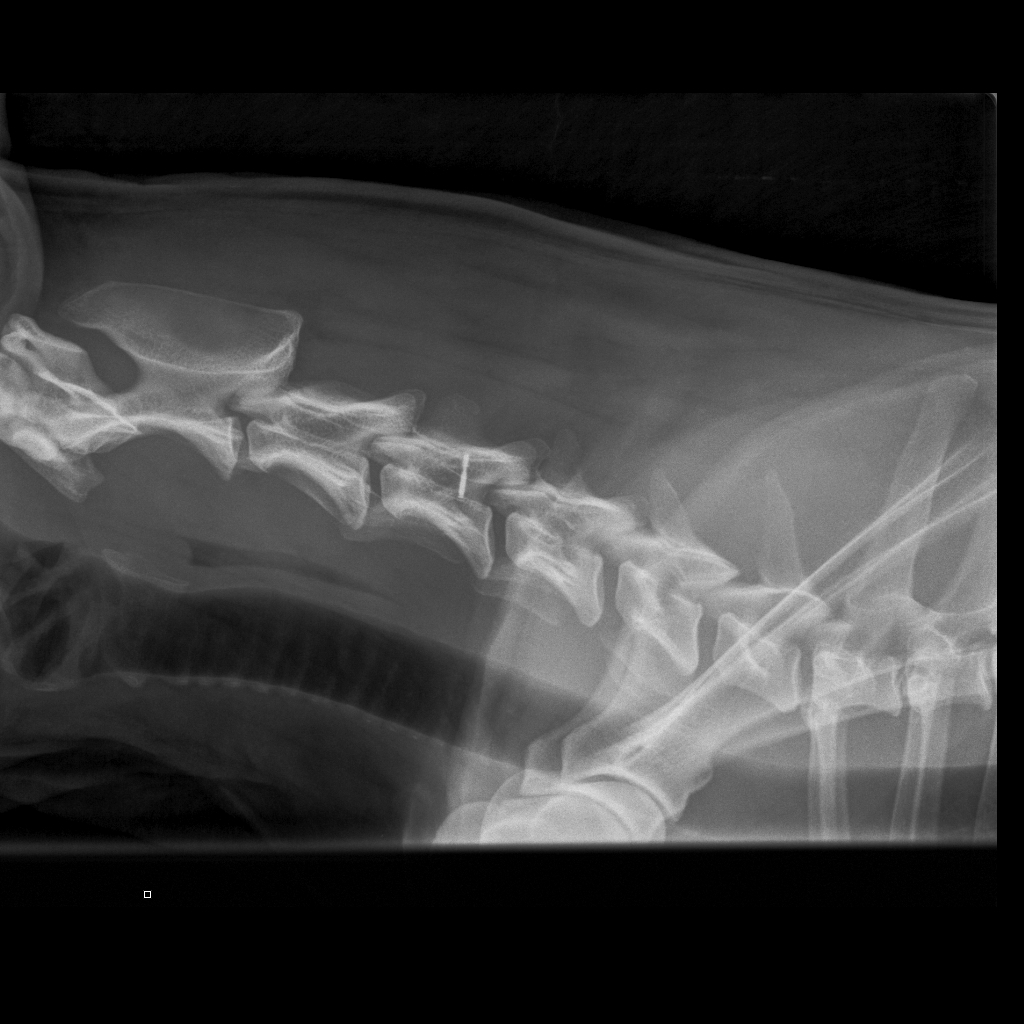

Koko selkä kuvattu terveeksi toistamiseen 1.9.14:

kaularanka

rintaranka

lanneranka

* * * *

Quti viety lääkäriin, koska vingahtelee kääntäessän päätään. Koko selkä kuvattiin, ei muutoksia. Oireiden jatkuessa kaularanka

magneettikuvattiin. Kuvanneen eläinlääkärin mielestä Nomilla on välilevyrappeuma ja kaikki harrastaminen mietittävä uudelleen.

Halusimme toisen mielipiteen Timo Talviolta, joka halusi ottaa Nomin kaularangasta taivutuskuvat. Talvion mukaan kyseessä ei ole

välilevyrappeuma vaan taivutuskuvissa näkyy kaularangan nikamien 5 ja 6 välillä liukuma. Lääkekuurin ja levon jälkeen voi

harrastamista jatkaa normaalisti. Talvion lausunto:"Kyse on nikamien välisestä "löysyydestä". Selkärangan rakenteelliset

viat ovat pääsäänöisesti perinnöllisiä, mutta tällainen lievä nikamien välinen liikkuvuus ei sellaisenaan ole perinnöllistä,

toki perintötekijät voivat altistaa tämänkaltaisen tilan kehittymiseen."